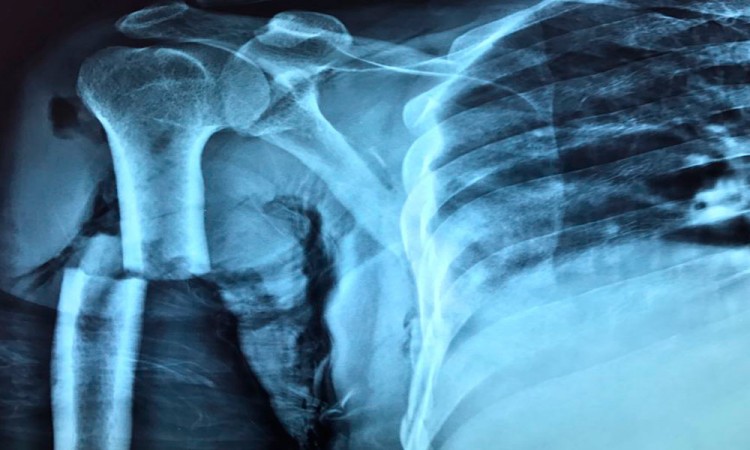

El otro lesionado, Miguel García Antonio, presenta una fractura en el brazo derecho, por ello también tuvo que ser intervenido quirúrgicamente. Se le reporta estable, pero no podrá trabajar por un tiempo.